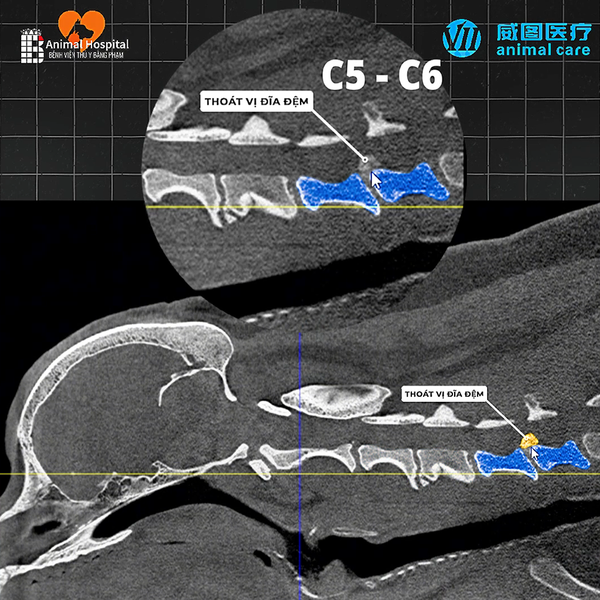

- Khi có nghi ngờ tổn thương phức tạp ở xương, khớp hoặc cột sống, ví dụ: gãy xương khó, trật khớp, thoái hóa khớp, biến dạng khớp.

- Khi cần lập kế hoạch phẫu thuật hoặc đánh giá trước và sau điều trị – CT cung cấp ảnh 3D và thông tin rõ nét về vị trí, kích thước và mối quan hệ của tổn thương.

- CT Scan được chỉ định khi bác sĩ cần hình ảnh chi tiết hơn về mô mềm, hộp sọ, xoang mũi, phổi, ổ bụng hoặc hệ thần kinh.

- Hình ảnh 3D nhiều lát cắt, nhìn rõ cấu trúc sâu bên trong cơ thể.

- Phát hiện tổn thương nhỏ, viêm, u hoặc dị tật mà X-quang không thể thấy.

- Cho phép đo chính xác kích thước và vị trí tổn thương trước phẫu thuật.

🔍7. Hình Ảnh Thực Tế – Kết Quả Sau Khi Chụp

Hình ảnh CT thể hiện chi tiết từng lớp cấu trúc trong cơ thể, giúp bác sĩ:

- Xác định chính xác vị trí khối u, ổ áp xe, hoặc chấn thương sâu.

- Lên kế hoạch phẫu thuật hoặc điều trị nội khoa chính xác.